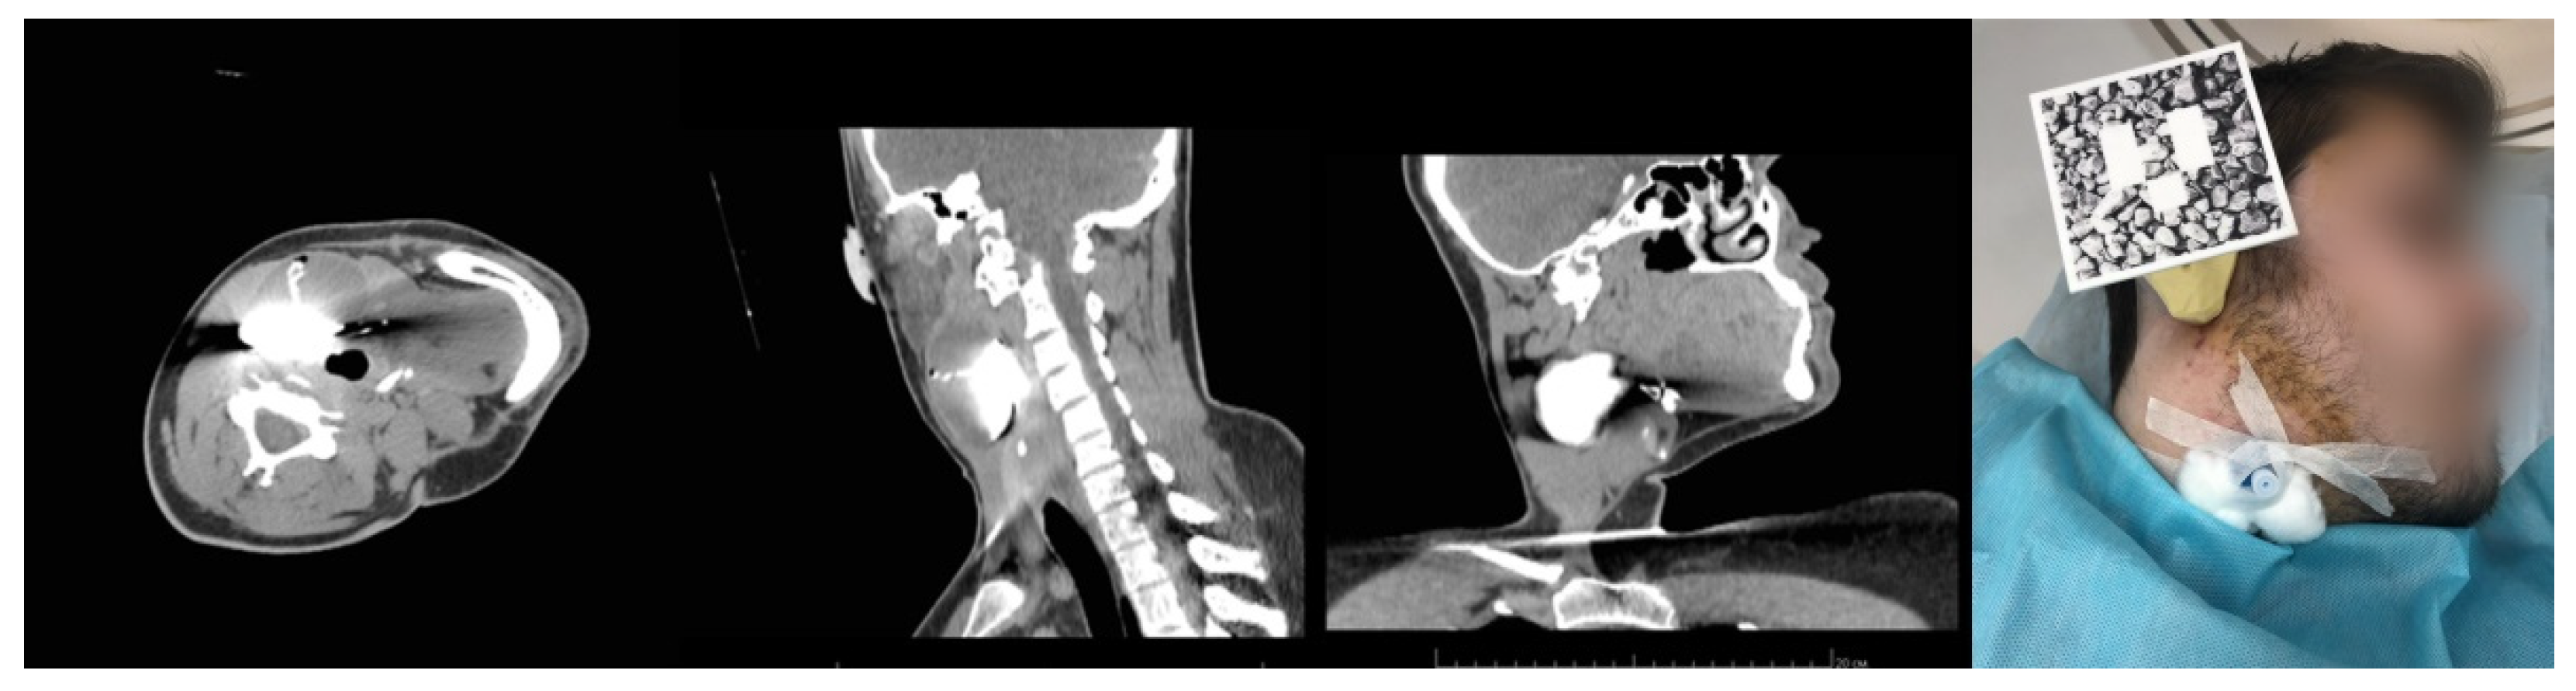

3.2. Case 2. Adjustable Navigation Frame

Operating Principle and Conclusion

3.3. Case 3. Adjustable Navigation Frame

- Despite the rigid fixation of the patient in Case 1, Cases 2 and 3, which involved no rigid immobilization of the patient relative to the operating table, demonstrated the best accuracy for hologram referencing. We attribute the obtained results to the variants of the reference marker’s attachment to the patients’ body parts and its relation to the surgery area. The closer they were to each other, the more accurately the hologram could reference to the real landmarks.